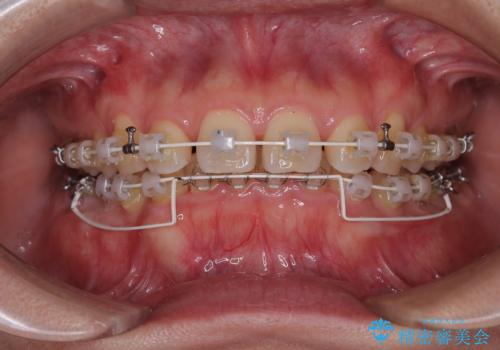

咬合力が強いことと、マウスピースを長時間装着する自信がないとのことで、ワイヤー装置にて矯正治療を行うこととしました。

下顎臼歯を起き上がらせるためにユーティリティーアーチを使用し、一気に深い咬み合わせを改善することができました。